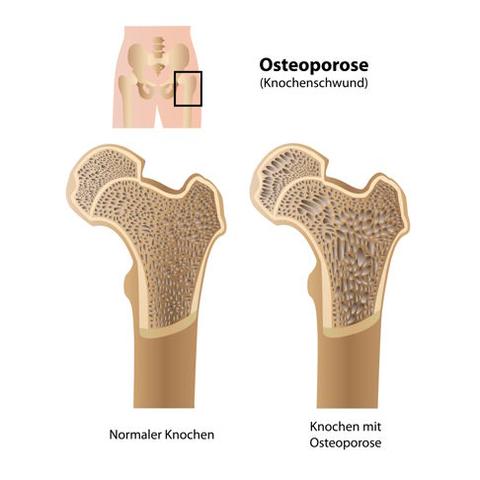

Osteoporose wird gefährlich, wenn der Verlust an Knochenmasse über das normale Maß hinausgeht und der Knochen schneller abbaut als erneuert wird. Dies führt zu porösen Knochen, die weniger stabil sind und leichter brechen können. Besonders gefährlich sind Knochenbrüche in der Wirbelsäule, im Hüft- oder Oberschenkelbereich, da sie mit starken Schmerzen und Einschränkungen der Mobilität einhergehen können.

Ein wichtiger Faktor für die Schwere der Osteoporose ist das Ausmaß des Knochenschwunds. Je mehr Knochenmasse verloren geht, desto poröser und instabiler werden die Knochen. Dadurch steigt das Risiko für Knochenbrüche, insbesondere an stark belasteten Stellen wie Hüfte, Wirbelsäule und Handgelenken.

Der Knochenschwund bei Osteoporose kann zu ernsthaften Komplikationen führen und die Lebensqualität erheblich beeinträchtigen. Wenn die Knochenmasse über das normale Maß hinaus abnimmt und der Knochenabbau schneller als der Aufbau erfolgt, werden die Knochen porös und weniger stabil. Dadurch steigt das Risiko für gefährliche Knochenbrüche deutlich an.

Die Osteoporose kann in verschiedene Stadien eingeteilt werden, je nachdem wie stark der Knochenschwund bereits fortgeschritten ist. Im Frühstadium sind die Veränderungen im Knochen noch nicht stark ausgeprägt und es treten meist keine oder nur wenige Symptome auf. In diesem Stadium ist das Risiko für Knochenbrüche noch relativ gering.

Im mittleren Stadium hat sich der Knochenschwund bereits weiter fortgesetzt und es können erste Beschwerden auftreten. Es besteht ein erhöhtes Risiko für Knochenbrüche, insbesondere an den Wirbelkörpern und am Handgelenk.

Im fortgeschrittenen Stadium ist der Knochenschwund sehr stark ausgeprägt und es kommt vermehrt zu Knochenbrüchen. Die Symptome sind deutlicher spürbar und es kann zu einer Einschränkung der Beweglichkeit kommen.